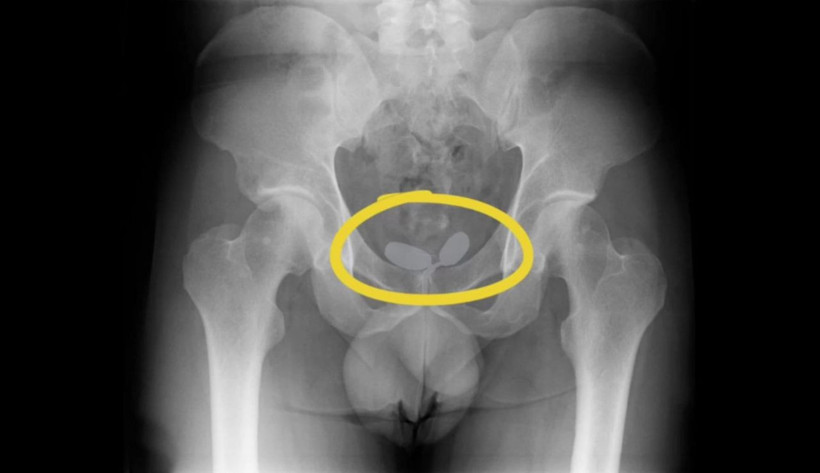

Alınan istihbarat doğrultusunda 2’si yabancı uyruklu toplamda 5 kişi yakalanarak gözaltına alındı. Yapılan röntgen muayenesinde, uyuşturucu kaçakçılarının akıl almaz oyunu ortaya çıktı.

Yapılan röntgen muayenesinde, Alman uyruklu kadının cinsel organında prezervatifler içerisine gizlenmiş uyuşturucular ele geçirildi.

Diğer Alman yabancı uyruklu erkeğin ise uyuşturucuları anüsüne gizlediği belirlendi. Yapılan muayene sonrası; 21,19 gram eroin, 12,70 gram kokain, 7,76 gram amfetamin, 7 adet sentetik ecza ele geçirildi.